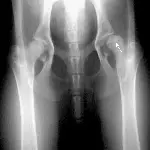

Figure 4A. A 5-year-old, male Brittany spaniel with a 2-month history of lameness. The opposite elbow was normal. A fracture line cannot be seen in this anteroposterior view of the elbow.

Figure 4B. A hairline intercondylar fracture (arrow) can be seen after repositioning the elbow and x-ray beam only slightly. This may represent incomplete ossification or a true fracture. In this case, the hairline fracture was confirmed by bone scan and arthroscopy.